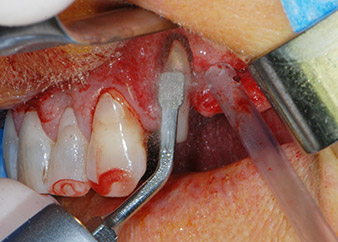

След един месец, в деня на операцията, болката и възпалението в зъб 24 е минимално, но подвижността в Miller class 2 е на лице. След отваряне на ламбата и почистването на периапикалната и перирадикуларната тъкани, обхватът на костния дефект стана очевиден (Фиг. 2 и 3).

В букалния корен, цялата вестибуларна и дистална кост липсва. Захващането е значително ограничено до палатиналния корен, подчертавайки предварително лошата прогноза. Зъб 27 също откри намалено хоризонтално захващане и минимално апикално разреждане (Фиг. 1) без клинични симптоми.

Въпреки това, ние се придържахме към първоначалния си план да запазим и двата зъба като абатмънти за временен мост по време на 6-месечната остеоинтеграция на имплантите. При повторна интервенция, ситуацията трябва да се преразгледа. Първо, в опит да се овладее ендо-перио проблема, останалата повърхност на зъба е внимателно обработена с пиезохирургично оборудване (Piezomed, W&H, използван с накрайник S1 под формата на шпатула, първоначално проектиран за ерозия на латералната синусна стена) (Фиг. 4).